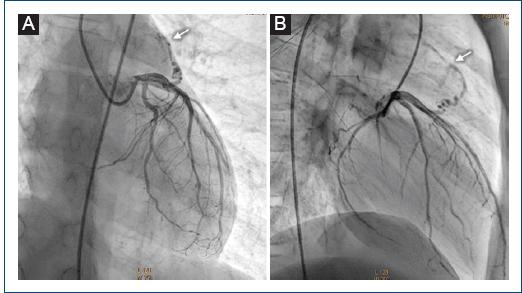

Figura 3 Coronariografía izquierda que muestra una fístula coronaria que se origina en el tercio proximal de la descendente anterior y que llega al tronco pulmonar (flecha). A: proyección oblicua anterior derecha a 20°. B: proyección oblicua anterior derecha a 70°.

Varón de 11 años al que se detectó un soplo cardiaco a la edad de 8 años por médico pediatra, quien comentó al familiar que este era un soplo «inocente» y se le dio vigilancia por 3 años. Al no modificarse el soplo con el tiempo, es enviado a nuestra institución, asintomático cardiovascular. Exploración física: buen crecimiento y desarrollo, soplo expulsivo II/IV, en mesocardio, tono agudo, timbre piante, sin modificación con maniobras, hígado no congestivo, pulsos normales en las cuatro extremidades, resto de la exploración sin alteraciones. Electrocardiograma y telerradiografía de tórax normales. Ecocardiograma transtorácico con presencia de flujo continuo retrógrado por Doppler color de 1 mm que llega al tronco de la arteria pulmonar, sin lograr determinar su origen (Fig. 1 A y B). La angiografía por tomografía computarizada (angio-TC) de tórax reporta una estructura vascular delgada, elongada, que comunica aparentemente la aorta ascendente con el tronco de la arteria pulmonar (Fig. 1 C). Se propone cateterismo cardiaco diagnóstico. En la angiografía de la aorta ascendente y en coronariografías selectivas se aprecia una fístula coronaria que nace inmediatamente después del ostium de la coronaria derecha, de 1 mm de diámetro, con un trayecto anterior e izquierdo sobre el infundíbulo pulmonar, drenando a la parte proximal del tronco pulmonar por arriba del anillo valvular pulmonar (Fig. 2 A y B), y una segunda fístula con origen en el tercio proximal de la arteria coronaria descendente anterior de 1 mm, drenando de igual forma en el tronco de la arteria pulmonar (Fig. 3 A y B), ambas de 0.15 mm a su llegada al tronco pulmonar. Debido al tamaño tan pequeño de las fístulas, se decide no realizar intervencionismo y continuar la vigilancia.